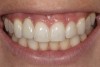

Fig 1. Midfacial recession can affect the esthetics of a smile and lead to an unsatisfactory outcome.

Figure 1

Fig 2. The cause for midfacial recession is excessive labial implant placement. Secondary to poor placement is overcontouring of the implant abutment.

Figure 2

Problem: The implant is placed too facial with significant recession on the midfacial aspect of the abutment and/or crown; the implant is healthy and the patient has a high smile line with an intermediate to thick periodontal phenotype (Figure 1 and Figure 2).17-19